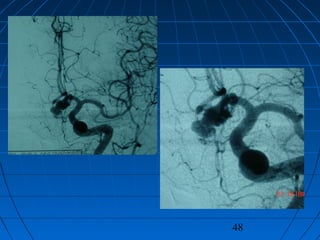

 56 yaşında erkek hasta56 yaşında erkek hasta

 BaşağrısıBaşağrısı (kronik-progresif, yaklaşık bir(kronik-progresif, yaklaşık bir

yıldır)yıldır)

 Nörolojik bakımdan normalNörolojik bakımdan normal

 Kranyal MRG:Kranyal MRG:

 pitüiter macroadenompitüiter macroadenom

 insidental AComA anevrizmasıinsidental AComA anevrizması

46

47

48

CERRAHİCERRAHİ

 Sol pterional trans-sylvian yaklaşımSol pterional trans-sylvian yaklaşım

 AcomA Anevrizması kliplendiAcomA Anevrizması kliplendi